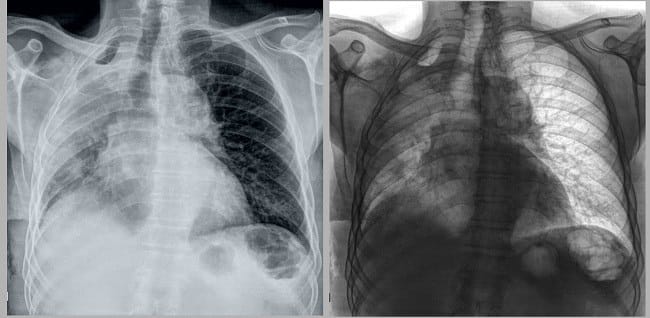

- Pemindaian dengan Rontgen atau CT scan dada, untuk mengetahui kondisi paru-paru